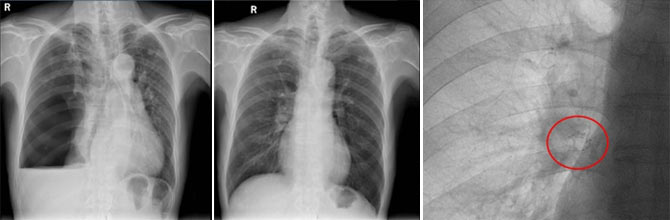

左图:2025-12-03入院前右侧液气胸,右肺压缩约90%。

中图:2025-12-31出院10天后,门诊复诊,右肺完全复张。

右图:红色圈中放大可见右肺下叶置入EBV活瓣。